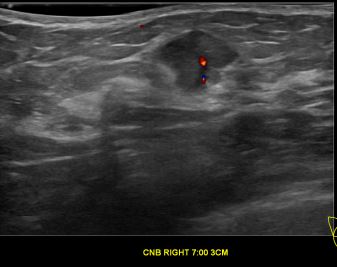

상기환자는 우측 유방 만져지는 멍우리로 내원하신 40대후반 여성분으로 의심스러운 우측혹 조직검사 시행해 유방암으로 진단되었습니다